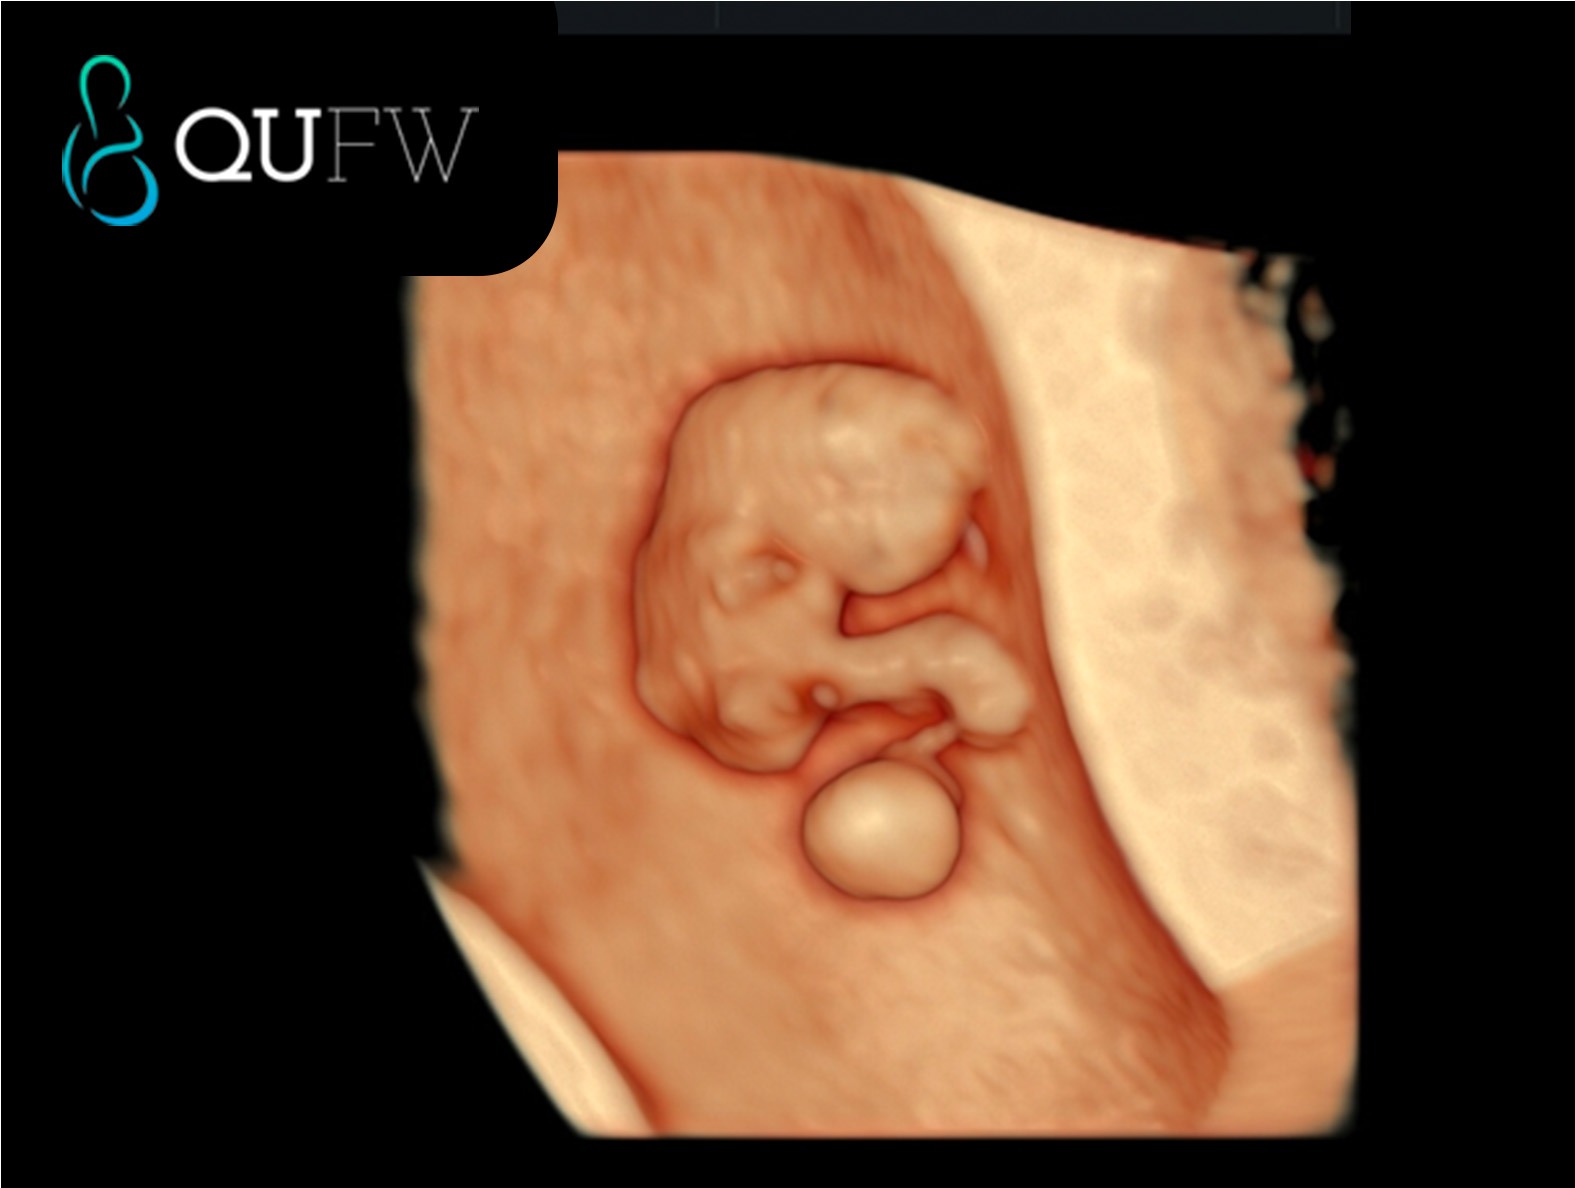

3D image of an 8 week fetus

- Detecting the Embryo: The embryo itself can usually be visualised after 6 weeks of gestation.

- Visualising the Heartbeat: One of the most significant markers of a viable pregnancy is the detection of the baby’s heartbeat, which can be seen through an ultrasound scan from around 6-7 weeks.